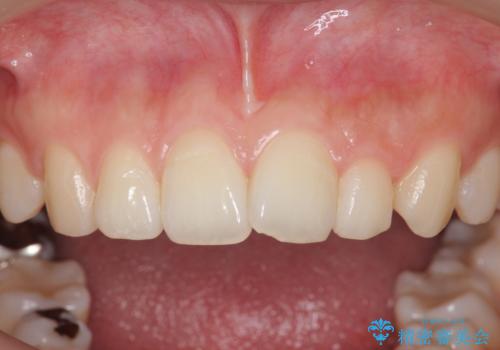

- 30代男性

- 歯ぎしりが気になるとの事で来院。

しっかりしたナイトガードが欲しいとの事だったので自費のナイトガードのご案内をしました。

ナイトガードは夜寝ている時、無意識に歯ぎしりをして歯がすり減ることを防ぐことがあります。また、歯が割れたり欠けたりするのも防いでくれます。